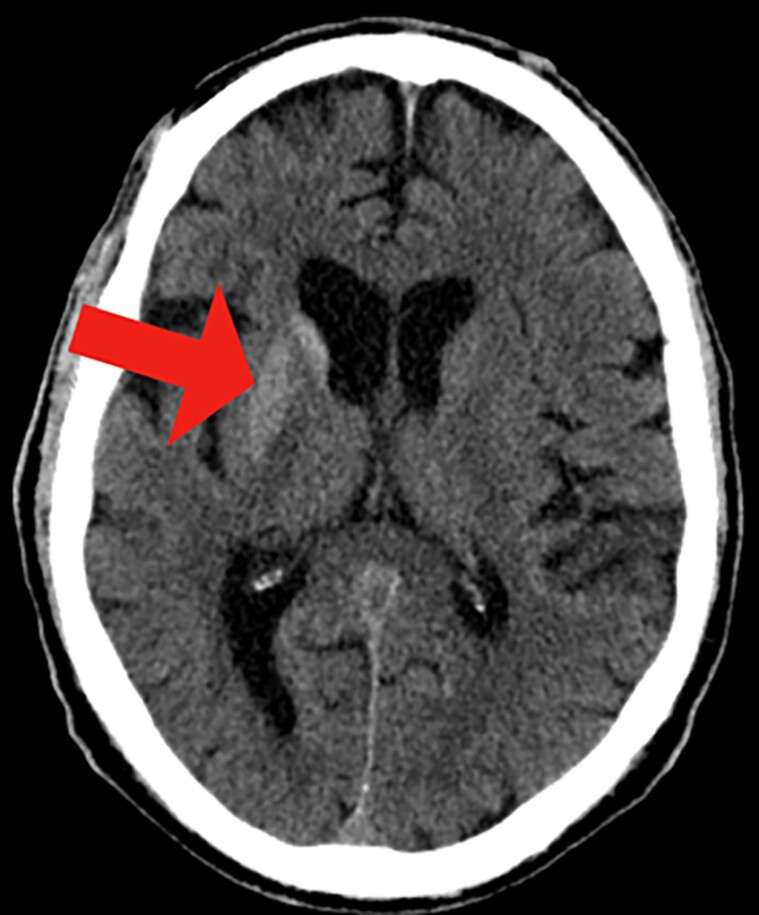

Nonketotic hyperglycemia chorea-ballismus (NKH-CB), a rare metabolic syndrome, arises as a secondary condition to hyperglycemia. It is marked by acute or subacute hemichorea-hemiballismus, hyperglycemic state, and unique reversible striatal abnormalities on neuroimaging. This case presents a 70-year-old Hispanic man with a significant medical history of cerebral vascular accidents, hypertension, bipolar disease, and uncontrolled type 2 diabetes mellitus. Notably, the patient was experiencing large-amplitude involuntary movements on his left side for the past 3 weeks. With resolution of hyperglycemia, the amplitude and frequency of the involuntary arm movements were absent. This case highlights the need for careful monitoring and tight control of blood glucose levels in patients with a history of diabetes, to prevent serious neurological complications such as NKH-CB syndrome. Prompt diagnosis through neurological evaluation, blood glucose level assessment, and neuroimaging techniques are critical in managing the symptoms effectively.

Abstract Image